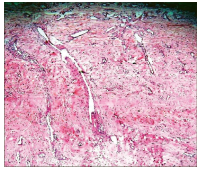

H&E staining and observation under 100X microscope shows large sinusoids varying in size, ranging from slit-like to ectatic with a staghorn configuration, poorly developed myoid-type cells surround the endothelial-lined vascular channels with absence of elastic lamina